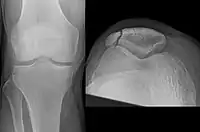

| A fracture of the patella seen on a lateral view | |